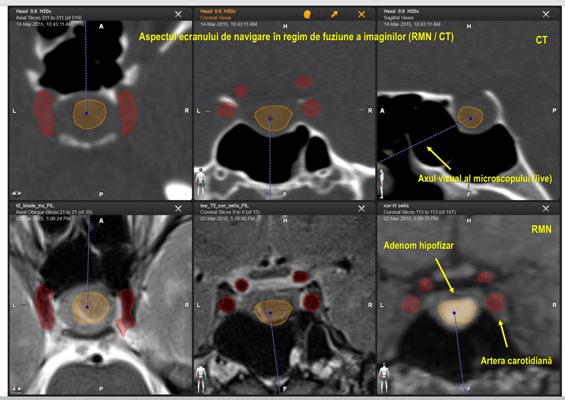

Sinusul sfenoidal și baza craniului în porțiunea anterioară se deosebesc printr-o varietate anatomică vastă, ceea ce face dificilă orientarea spațială în timpul operației. De aceea, s-au depus mari eforturi pentru a asigura precizia actului chirurgical în circumstanțe anatomice dificile. Pentru orientare, chirurgii foloseau radiografiile intraoperatorii, sondele ultrasonografice etc. Cea mai recentă tehnologie este neuronavigația fără cadru stereotaxic, considerată a fi GPS-ul neurochirurgului, disponibilă pentru toți pacienții din Republica Moldova în sala de operații Hybrid a Spitalului Clinic Republican. Acest sistem de neuronavigație a fost folosit și în cazul pacientei respective.